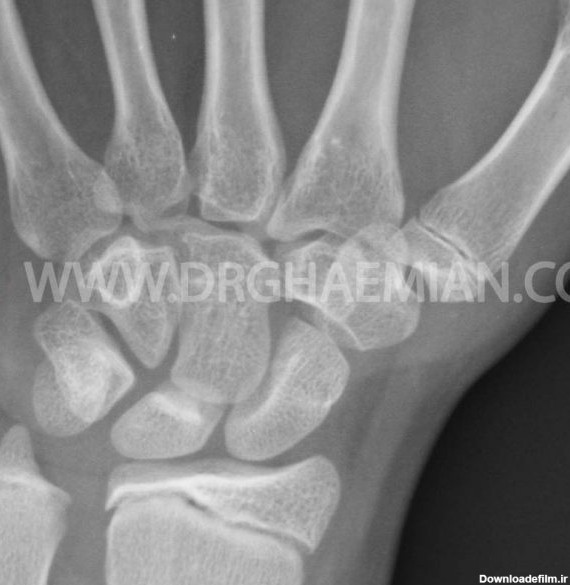

داشتن قد بلند آرزوی بسیاری از افراد است. افراد بسیاری برای رسیدن به این خواسته در سنین رشد به پزشک مراجعه می نمایند و خواستار این هستند که با روش های قد خود را افزایش دهند. رادیوگرافی ساده استخوان های مچ دست تجویز پزشک در این مواقع برای شماست. در واقع پزشک با مشاهده عکس مچ دست، سن استخوانی را تشخیص میدهد و میفهمد که آیا صفحه رشد استخوانهای فرد باز است و هنوز جای رشد دارد یا نه؟ در صورتیکه اگر سن استخوانی فرد بالا باشد و صفحه رشد بسته شده باشد، دیگر جایی برای رشد طولی استخوانها نخواهد بود. در انتهای استخوانها صفحهای به نام اپیفیز وجود دارد که در سنین رشد از جنس غضروف است و با تاثیر از هورمون رشد غضروفسازی میکند. با گذشت زمان این...

صفحه رشد چه کاری انجام می دهد؟ - علائم بسته شدن صفحه رشد - علائم صفحه رشد بسته - افزایش قد بعد از بسته شدن صفحات رشد چجوری ممکن است؟ + عکس صفحه رشد باز و بسته